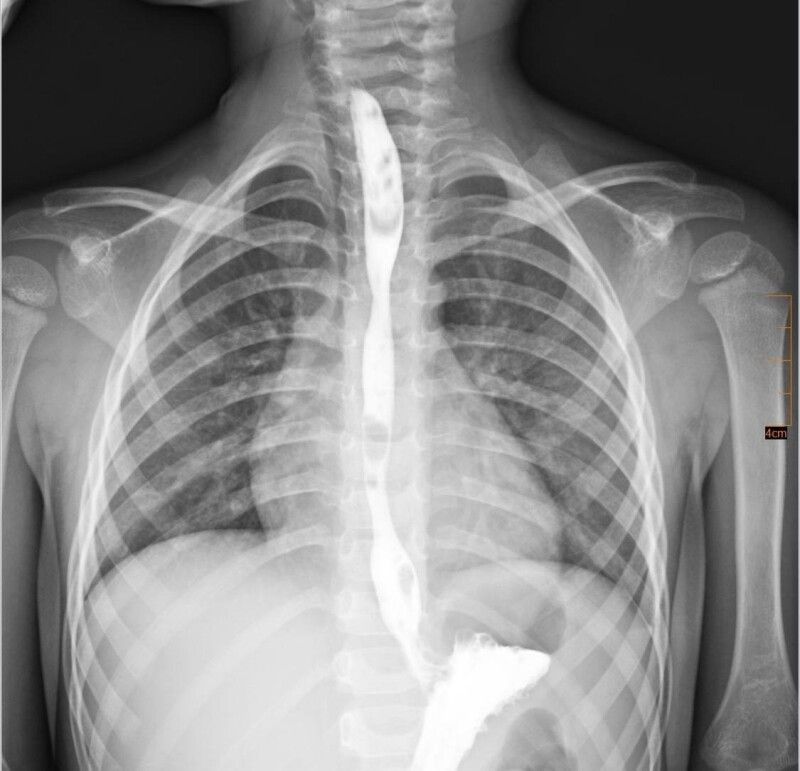

Дитина випадково проковтнула хімічну речовину з категорії побутової хімії, що призвело до тяжкого хімічного опіку стравоходу. На момент госпіталізації стан дитини був вкрай важким: вона не могла самостійно приймати їжу, страждала від вираженого болю, слинотечі та блювання. Малечу негайно госпіталізували до відділення інтенсивної терапії.

Згодом у дитини сформувався критичний стеноз стравоходу - значне звуження його просвіту, що повністю унеможливлювало прийом їжі через рот.

Після ретельного обговорення мультидисциплінарною командою було ухвалено рішення про проведення серії балонних дилатацій стравоходу - малоінвазивних ендоскопічних втручань, під час яких звужену ділянку поступово розширюють спеціальним балоном без виконання розрізів.